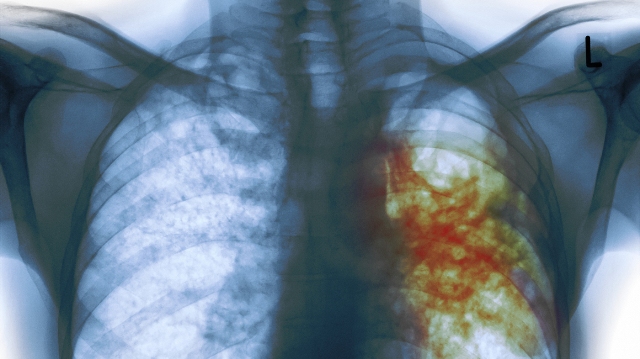

TB is the leading cause of death after HIV from infectious diseases and the WHO statistics shows around the world, there are about nine million new cases and two million deaths.